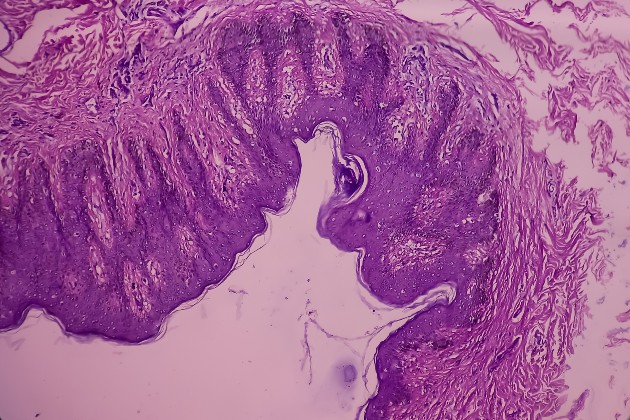

Endometriosis is a condition where tissue similar to the uterus lining (endometrium) is present outside the uterus. This can cause a chronic, inflammatory reaction and formation of internal scar tissue. Although the growths are benign, they can cause intense pain, chronic fatigue, heavy and painful periods, bowel issues and infertility. Endometriosis can be superficial or severe (where the endometrium are 5mm or thicker). Severity of the condition does not always correlate to severity of symptoms.